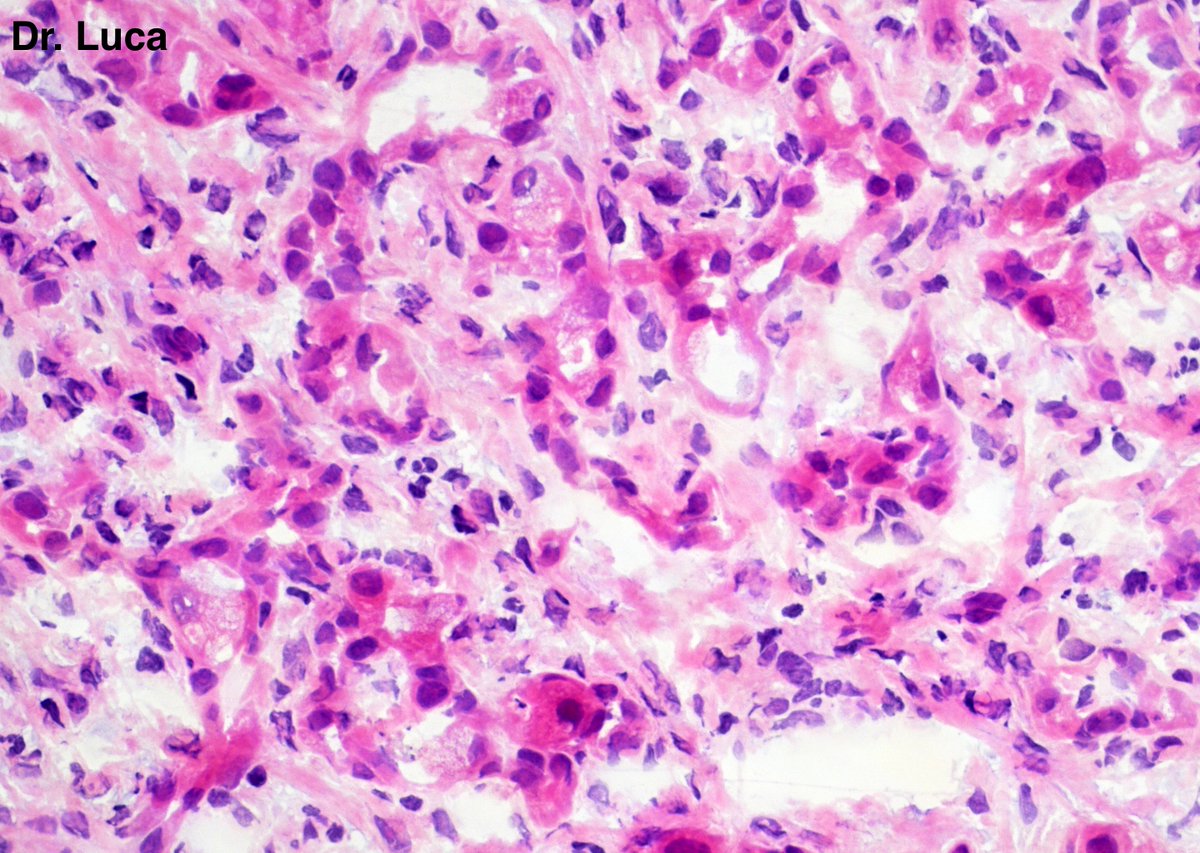

71yoM, bone metastasis, what's your quick H&E diagnosis? (no IHC) @AkgulMd @JPintoPath @slusagar @EKoubaMD @Pathmath1 @s_prendeville @goziemnweke @SumantaDas_7 @D4L14H @PoloniaAntonio @kriyer68 @md_kyle @kis_lorand @MarcosLepeMD @ivanaspath @pathobot #Pathology #PathTwitter

22

25

63